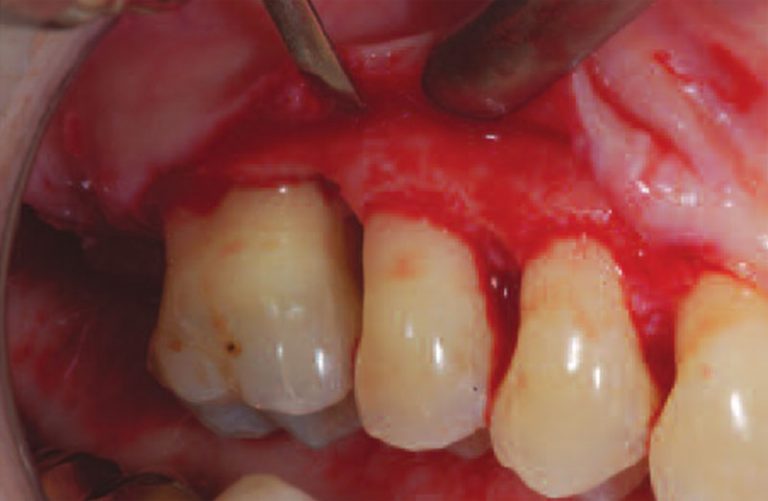

a Clinical view at baseline. b Intraoperative view of supra bony What Is A Suprabony Periodontal Pocket Periodontal pockets are also classified as suprabony and infrabony, depending on their relationship to the adjacent alveolar. We call this process a periodontal exam or probing. The periodontal pocket is a pathologically deepened gingival sulcus due to the apical migration of junctional epithelium. It may occur due to coronal movement of the gingival margin, apical. The suprabony pocket floor or. What Is A Suprabony Periodontal Pocket.